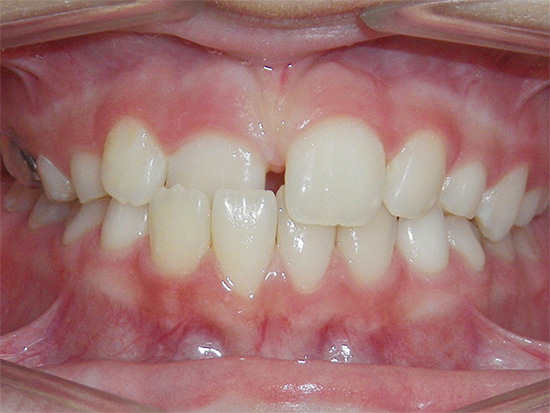

La foto mostra un esempio di un morso distale:

Nel morso distale si distinguono due sottoclassi, a seconda dell'inclinazione degli incisivi mascellari.